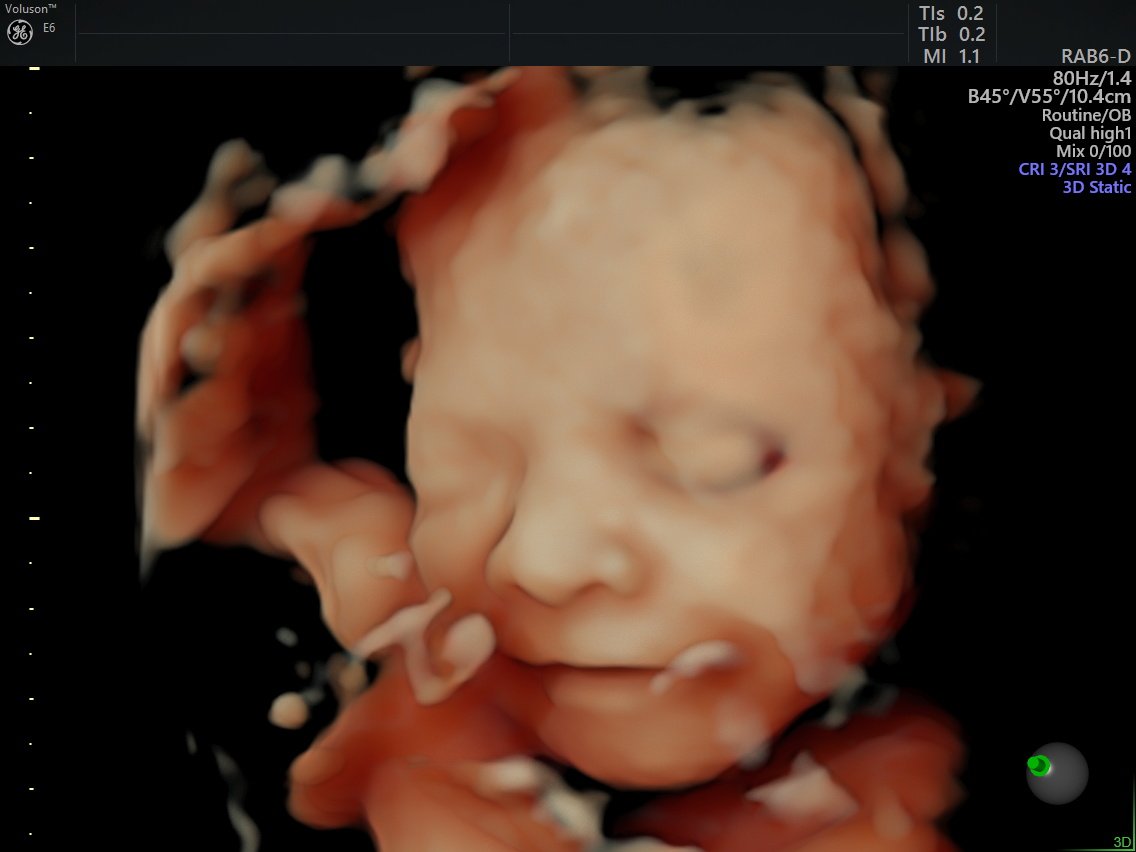

Week 28: This week we had a 3D Ultrasound and it was amazing. Although this is an elective ultrasound (meaning it is not covered by insurance), it was worth every penny. She was a little stubborn at first keeping her arm up by her face and her face buried in the placenta. After a little coaxing and jiggling we got some beautiful shots of our baby girl. I swear she has Krystal’s nose and lips and she is absolutely beautiful. We even got a little smile.